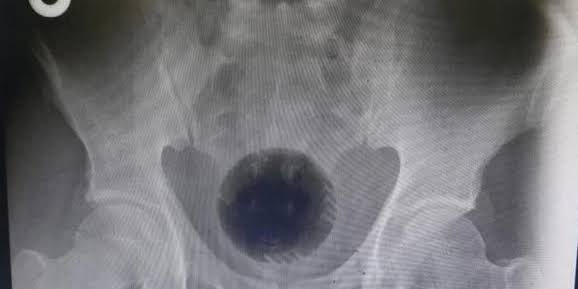

Homem é operado após inserir coco no 4nus para estimulação s5xual

Um homem de 56 anos inseriu um coco no ânvs e ficou por dois dias com a fruta alojada no local. O caso foi registrado em Taiwan e divulgado na revista médica British Journal of Surgery.

O paciente, que não teve a identidade divulgada, procurou um hospital após ficar dois dias constipado. Os médicos precisaram realizar uma cirurgia para remover o coco que teria sido usado para estimulação s3xual. Segundo os médicos, o paciente não conseguia urinar e queixou-se de fortes dores abdominais.

Os exames mostraram que a fruta estava alojada no reto, comprimindo a uretra e impedindo-o de urinar. A data do incidente não foi revelada no relato do caso pelos médicos do Hospital E-Da, na cidade de Kaohsiung, localizado no sul do pais. O coco de 9cm de comprimento, foi extraído por laparotomia, operação que envolve a abertura do abdômen.